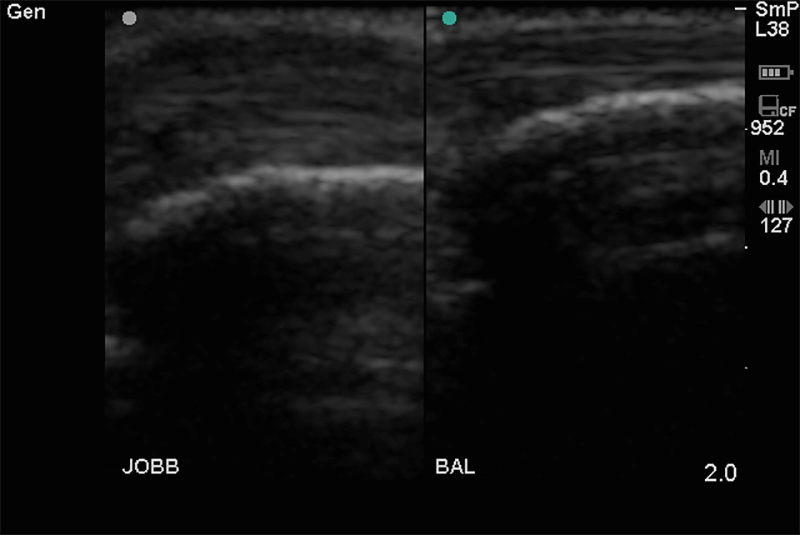

Alapvetően a pajzsmirigy, nyálmirigyek állapotának tisztázása mellett felvilágosítást ad a nyaki nagyerek állapotáról. Kimutathatóak a kóros nyirokcsomók, nyelvgyök körüli, szájfenék alatti, garatkörüli kóros elváltozások.

A nyaki régióban megjelenő kóros duzzanat, csomó fájdalommal vagy anélkül, szorító érzés a torok tájékán, rekedtség és esetleg nyelési zavar utalhat az itt található szervek kóros folyamataira.

A kóros tágulatok és szûkületek, thrombusok, az erek részleges vagy teljes elzáródása kimutatható, mérhető. Érvizsgálataink a nyaki (carotis) erek állapotának tisztázására vonatkoznak.

Az érelmeszesedés korai stádiumban való felismerése a súlyos szövődmények megelőzése érdekében rendkívüli fontossággal bír. A már kialakult érbetegségekben az ultrahang a terápia megválasztásához feltétlenül szükséges.